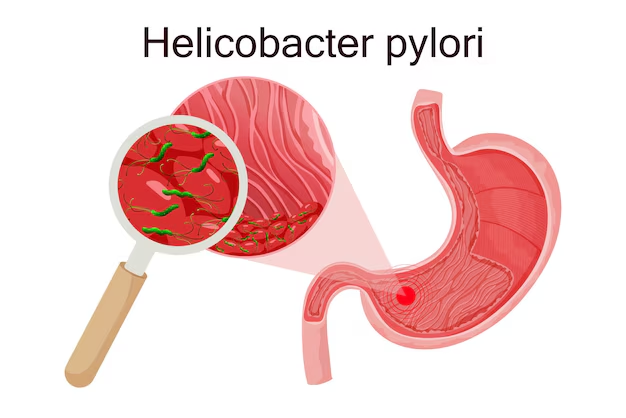

ما المقصود بالتهاب الكبد الفيروسي؟

التهاب الكبد الفيروسي هو عدوى تصيب الكبد نتيجة دخول فيروس إلى الجسم، مما يؤدي إلى حدوث التهاب في أنسجة الكبد قد يسبب تورمًا وألمًا في بعض الحالات. ويوجد عدة أنواع من هذه الفيروسات تُعرف بالحروف من A إلى E، ويختلف كل نوع في طريقة انتقاله وتأثيره. يمكن أن يكون هذا الالتهاب مؤقتًا ويختفي خلال فترة قصيرة، أو يستمر لفترة طويلة ويتحول إلى حالة مزمنة. كما قد ينتقل من شخص لآخر عبر الدم أو بعض الممارسات غير الآمنة، لذلك من المهم فهمه جيدًا واتخاذ الاحتياطات اللازمة للوقاية منه.